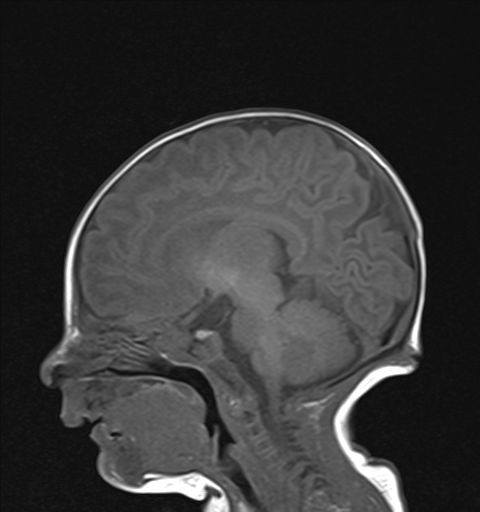

El cuarto día de ingreso, en contexto de irritabilidad sin fiebre, se realiza una analítica, con negatividad de reactantes de fase aguda y hemocultivo. Comentado el caso al servicio de neurocirugía, se descarta la intervención quirúrgica en ese momento, manteniendo el seguimiento ambulatorio en consultas y pendiente de planificación quirúrgica. La paciente, al alta, también es seguida en la consulta de Neuropediatría, encontrándose asintomática, con exploración y desarrollo psicomotor normal. A los cuatro meses de vida, se realiza una RM craneal de control (Fig. 3), previa a la cirugía, que sigue mostrando el seno dérmico sin otras complicaciones.

| Figura 3. Trayecto del seno dérmico subcutáneo en resonancia magnética craneal de control (secuencia T1 sin contraste intravenoso) |

|---|

![]() |